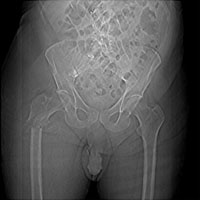

- Click on the image for a larger versionCAP radiograph of the pelvis. This is a different patient with prostate cancer. There are multiple sclerotic metastases.